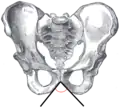

![]() حوض الذكر (ويشار إلى القوس العانية) حوض الذكر (ويشار إلى القوس العانية) | |